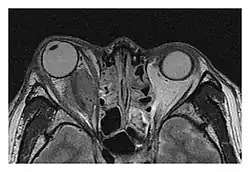

| Mass lesion around the right optic disc in a 44-year-old man with IgG4-related ophthalmic disease and a serum IgG4 of 599 mg/dL.[1] (T2-weighted MRI) | |

The extent of inflammation that can occur in IgG4-ROD is well demonstrated on magnetic resonance imaging (MRI).